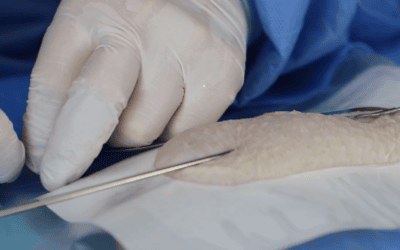

Conocer el comportamiento del ultrasonido en función de los tejidos atravesados es especialmente útil para evitar posibles errores de interpretación de la imagen y una mala elección del lugar de punción. Permite entender mejor qué está pasando en el momento del mapeo vascular pero también durante la inserción de la aguja en vena, lo cual conlleva a una mejor prevención del fracaso de colocación del acceso vascular.